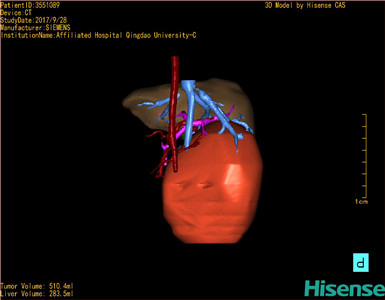

CT结果输入海信CAS系统后行3D重建及手术规划后,于2017-10-10全麻下行“肝肿瘤切除术”手术治疗:

将0.625mm双源薄层CT资料的静脉期和动脉期Dicom格式文件导入海信CAS系统。

通过调节窗宽窗位调整CT序号,对肿瘤,肝实质,胆囊,下腔静脉,肿瘤,肝动脉、门静脉及肝静脉等进行三维重建;系统自动计算肿瘤体积和肝脏体积。

模拟手术操作,自动计算切除肿瘤体积。肝脏体积为453.7ml,通过比对2-3岁正常肝脏体积为475.97±99.7ml,通过术前模拟手术,精准判断切除后剩余肝脏体积能耐受,避免肝衰竭发生。

术前三维重建:

重建图片